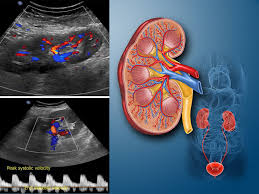

بررسی جریان خون به کلیهها و عملکرد کلیه ها

(درصورت نیاز به بررسی بیشتر،ارجاع به متخصص نفرولوژی درمنزل انجام می شود)

(مفید برای بیماران فشار خونی یا کلیوی).